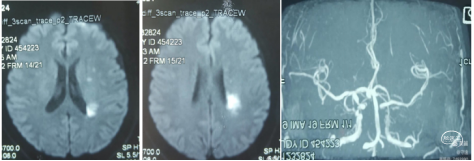

典型病例1: 患者,mshq 男性,44岁,“突发右侧上下肢无力,言语含糊”,溶栓后肢体肌力4-级,搀扶行走。经基层医院静脉溶栓后转入我院。外院核磁显示:左侧侧脑室后角梗塞。MRA显示:C4-C5段以远血管显影浅淡。

转入我科后,患者肢体较溶栓后略有加重,右下肢肌力3级,上肢2级。造影显示:左侧颈内动脉C1段呈火苗样窜动,提示:远端闭塞可能。说明病情在持续加重,可能为血栓堆积闭塞了血管。

入院后急查CT未见出血和低密度改变。核磁DWI示:左侧大脑半球梗塞,左侧大脑中动脉和内囊区域受累。MRA示:左侧颈内动脉未显影,考虑闭塞。